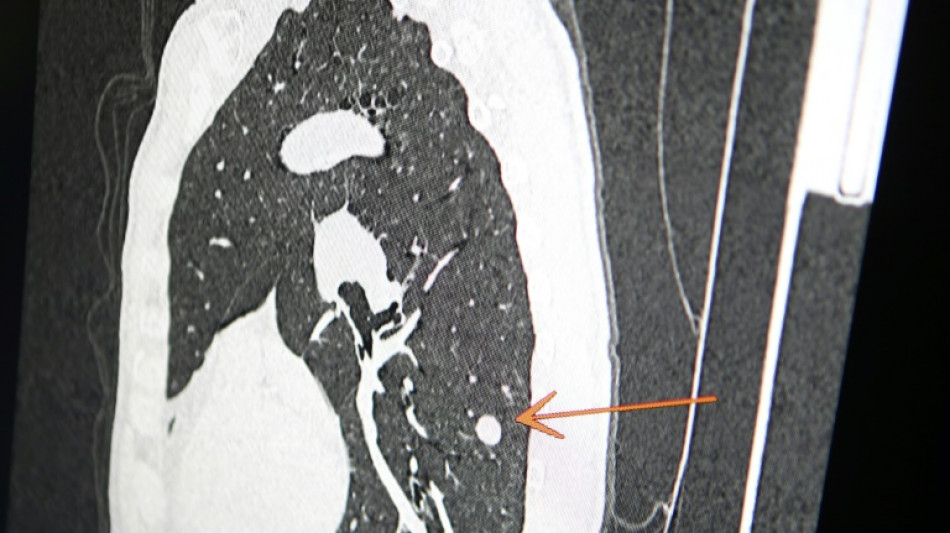

"Usted tiene cáncer", mensaje erróneo y aterrador a cientos de pacientes de una clínica en Inglaterra

Una clínica del norte de Inglaterra dio un gran susto a cientos de pacientes al enviar el mensaje "diagnóstico: cáncer de pulmón agresivo con metástasis" en lugar de sus buenos deseos de Navidad, informó el diario The Sun el jueves.

Según The Sun, entre los destinatarios del mensaje figuraba Chris Reed, un padre de familia de 57 años, que esperaba resultados de análisis para determinar si padecía cáncer de pulmón.